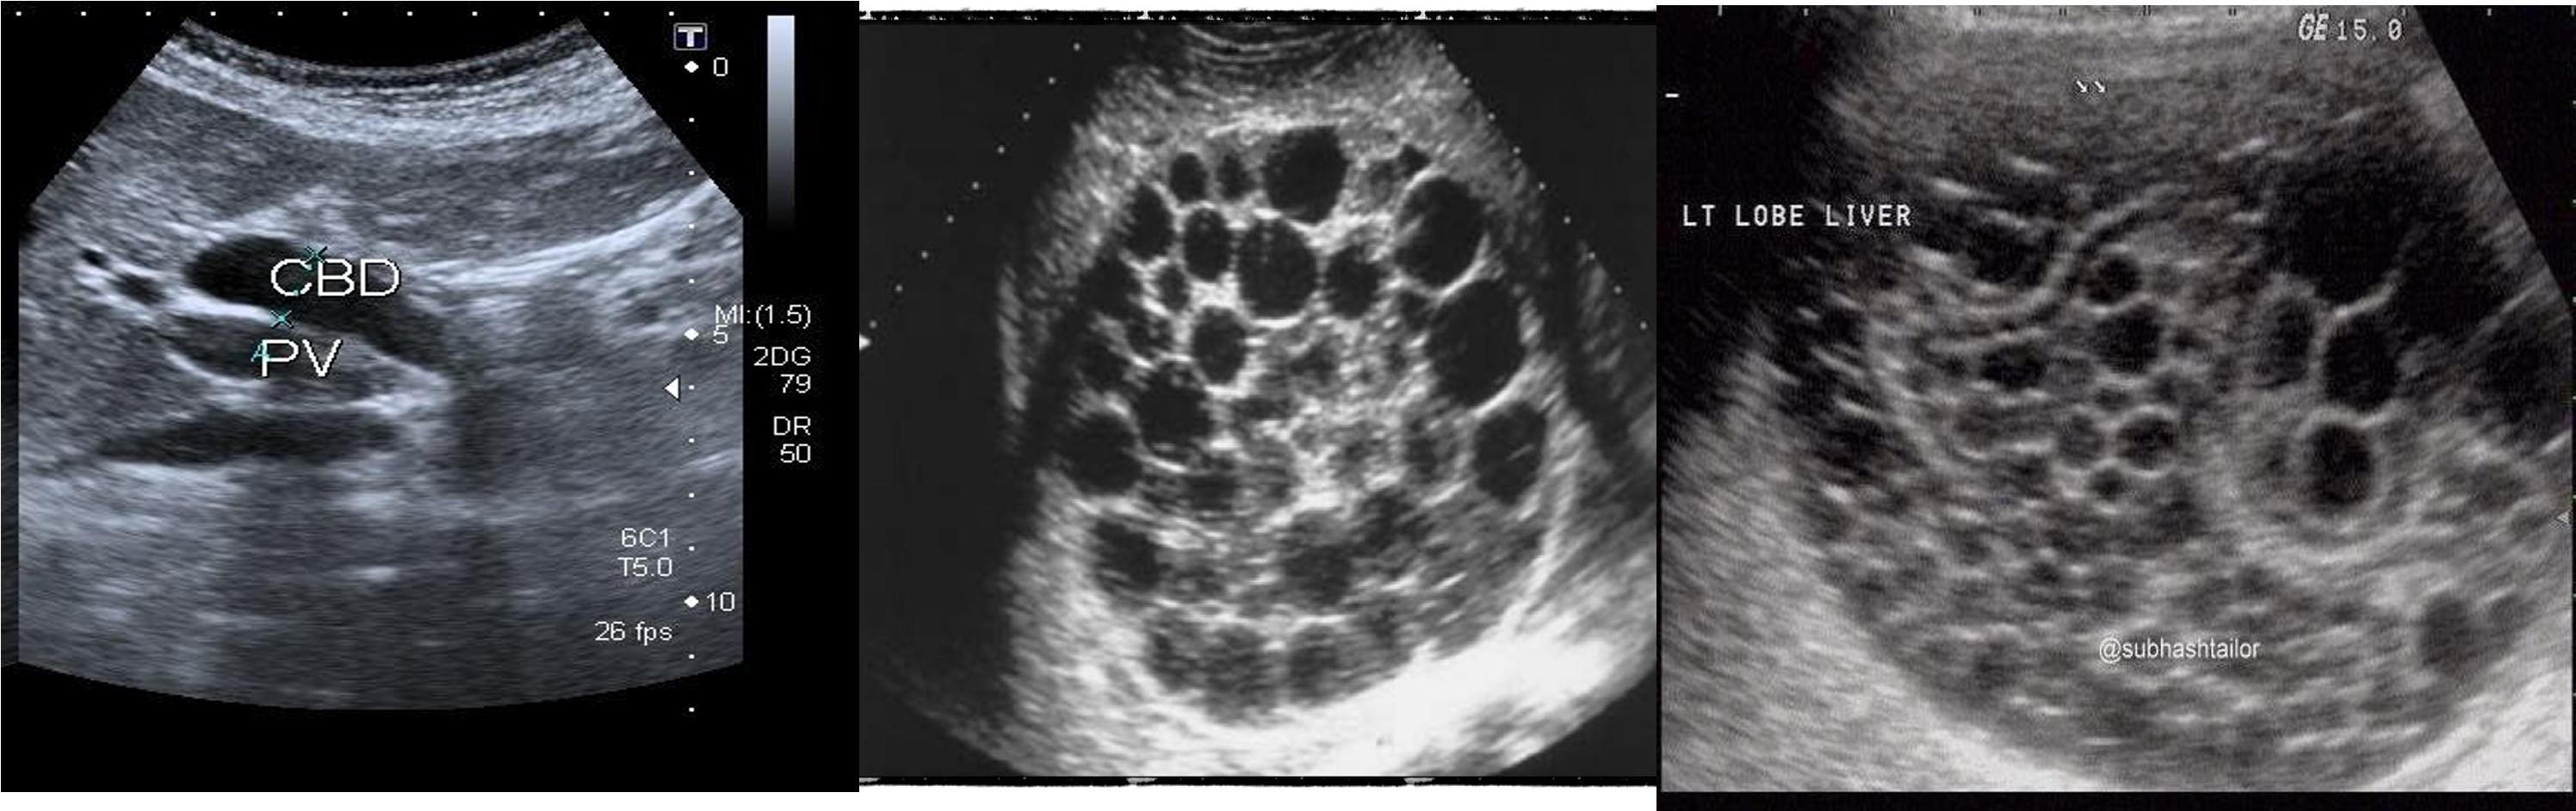

U/S

hydiatted

HCC

///